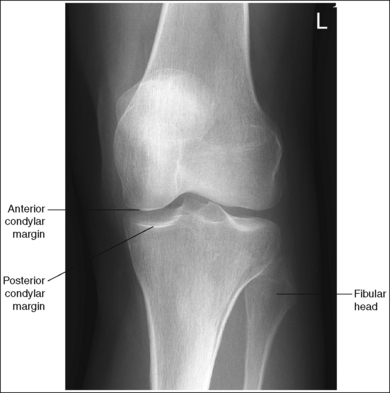

The knee demonstrates an AP projection. The medial and lateral femoral epicondyles are in profile, the femoral condyles are symmetrical, the intercondylar eminence is centered within the intercondylar fossa, and the tibia is superimposed over 0.25 inch (0.6 cm) of the fibular head.

• To obtain an AP knee projection, place the patient in a supine position with the knee fully extended. Internally rotate the leg until an imaginary line drawn between the medial and lateral femoral epicondyles is positioned parallel with the IR (Figure 6-71). This positioning places the medial and lateral femoral epicondyles at equal distances from the IR as well as medially and laterally in profile, respectively. It also centers the intercondylar eminence within the intercondylar fossa and draws the fibular neck and a portion of the fibular head from beneath the tibia.

• Effect of rotation. If the femoral epicondyles are not positioned parallel with the IR, an AP projection has not been obtained. If the patient's leg was not internally rotated enough to place the epicondyles at equal distances from the IR, they are not in profile, the medial femoral condyle appears larger than the lateral condyle, and the tibia is superimposed over more than 0.25 inch (0.6 cm) of the fibular head (see Image 54). If the patient's leg was internally rotated more than needed to place the femoral epicondyles at equal distances from the IR, the epicondyles are not demonstrated in profile, the lateral femoral condyle appears larger than the medial condyle, and the tibia is superimposed over less than 0.25 inch (0.6 cm) of the fibular head (see Image 55).

The knee joint space is open, the anterior and posterior condylar margins of the tibia are superimposed, the intercondylar eminence and tubercles are demonstrated in profile, and the fibular head is demonstrated approximately 0.5 inch (1.25 cm) distal to the tibial plateau.

• The anterior and posterior condylar margins of the tibia are superimposed if the correct central ray angulation, as determined by the patient's upper thigh and buttocks thickness, is used. By studying the tibial plateau region, you will see that the tibial plateau slopes distally approximately 5 degrees from the anterior condylar margin to the posterior condylar margin on both the medial and lateral aspects (Figure 6-72). Only if the central ray is aligned parallel with the tibial plateau slope is an open knee joint space obtained.

• Analysis of joint space narrowing. On an AP knee projection with adequate positioning, joint space narrowing is evaluated by measuring the medial and lateral aspects of the knee joint, which are also referred to as compartments. The measurement of each of these compartments is obtained by determining the distance between the most distal femoral condylar surface and the posterior condylar margin of the tibia on each side. Comparison of these measurements with each other, with measurements from previous images, or with measurements of the other knee determines joint space narrowing or a valgus or varus deformity. In a valgus deformity the lateral compartment is narrower than the medial compartment; in a varus deformity the medial compartment is narrower (see Images 56 and 57). Precise measurements of the compartments are necessary to ensure early detection of joint space narrowing and are best obtained when the knee joint space is completely open. If an inaccurate central ray angulation was used for an AP knee projection, the knee joint is narrowed or obscured, the intercondylar eminence and tubercles are foreshortened, and the tibial plateau is demonstrated.